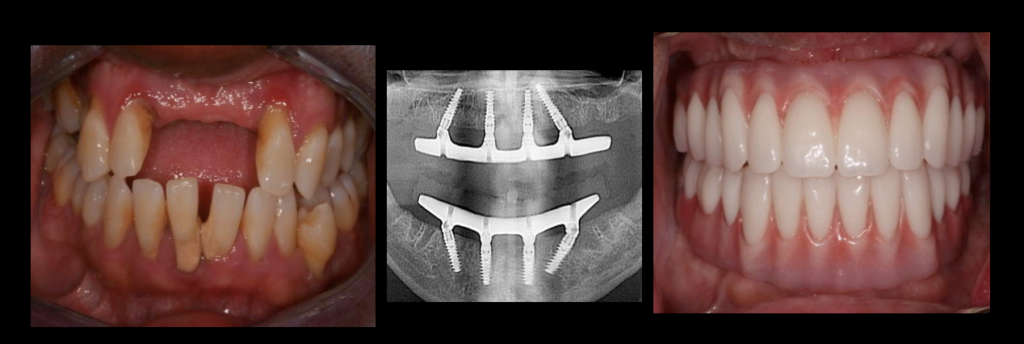

A full oral treatment typically consists of: Placing six to eight dental implants in the upper jaw. Four to six implants in the lower jaw.

Procedures for full implantation for dental implants in the mouth can range from about $ 7,000 to $ 68,000 in total. These types of implants have an average price of around $ 25,000. Keep in mind that getting a top or bottom set of full-mouth dental implants can cost anywhere from $ 3,500 to $ 30,000.